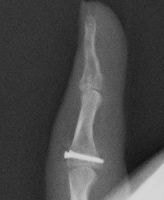

整形外科領域の手術において、骨を扱う際に必要なのがX線イメージです。当院では米ホロジック社製のフルオロスキャンを用いることにより、一般整形外科で用いる巨大なCアームでは見ることが困難な指骨の関節内骨折においても良好な整復操作を行うことを可能としています。